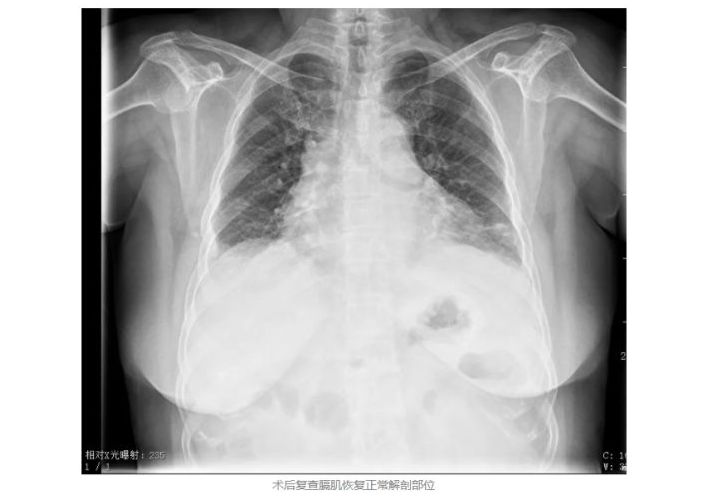

通过术前影像学检查可以明显看出左侧膈肌上移,压迫左肺,导致左肺压缩60%,胃肠同时被挤入胸腔。因而造成左肺不张,出现呼吸困难的症状。在明确诊断后,翟博教授为马女士安排了手术,但手术除了膈肌折叠,铺设补片以外,还存在很多难点,诸如手术过程中膈肌会随着呼吸运动,膈肌抬高距离操作点较远,皆影响操作;而左侧膈肌几近完全破坏,手术区域紧邻肺、心脏、肝脏、食道、腹主动脉、下腔静脉等重要结构,为此术者团队采用右侧站位,横向缝合,为减少创伤膈肌折叠时不打开膈肌平衡气压的损伤小,选用加长器械,长可吸收缝线,铺置补片时不降低气腹压,强调内侧充分打开左侧冠状韧带,补片固定于肋弓,内侧达心包,实现恢复膈肌功能与避免复发的双重目的。术中医疗团队利用腹腔镜微创技术,通过4个0.5-1cm的钥匙孔大小切口,采用“折叠缝合+补片加固”技术,将膨升的膈肌折叠收紧,重建胸腔腹腔正常解剖结构。

术后第一天查房时,马女士感激地说:“我现在胀气打嗝的情况都没有了,呼吸也顺畅多了,非常感谢哈医大四院普外科二病房翟博教授团队拯救了我的生命!”术后第二日,马女士既已康复出院,告别了疾病的困扰。